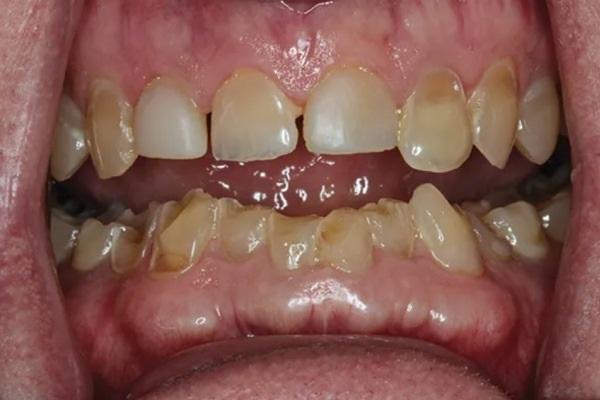

Мужчина, 54 года, был направлен к автору по поводу истирания зубных рядов и эрозии, которые, как предполагалось, были вызваны выраженным бруксизмом (Фото 1 и Фото 2). Его лечащий врач не был уверен, с чего начать планирование лечения, из-за предполагаемой сложности случая. Основной проблемой пациента был страх потерять часть или все зубы из-за обширного разрушения эмали (Фото 3). Были собраны снимки и подробные медицинские и стоматологические истории болезни, а также проведено детальное клиническое обследование. Полные снимки, фотографии и цифровые сканы были отправлены в зуботехническую лабораторию, и был разработан план лечения. У пациента было сильное желание действовать, и он принял этот план. Клинический случай был разбит на сегменты для обеспечения предсказуемой и более удобной реконструкции.

Фото 1: Фото улыбки анфас до лечения. Пациент хотел сохранить свои зубы и улучшить свою улыбку.